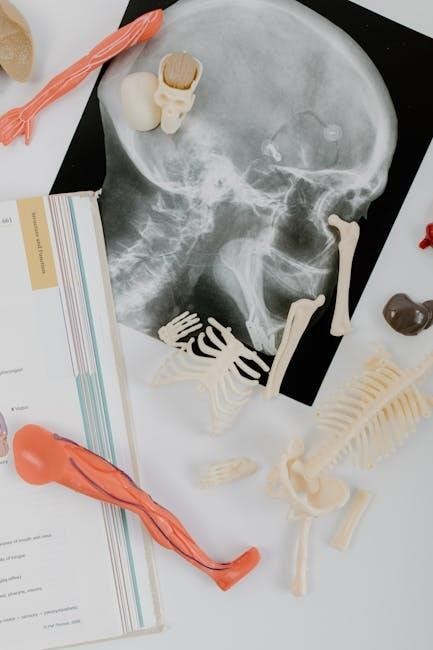

Anatomy and Physiology study guide PDFs dedicate significant sections to the nervous system, meticulously detailing its two primary divisions: the central nervous system (CNS) and the peripheral nervous system (PNS). The CNS, comprised of the brain and spinal cord, is explored through detailed diagrams and explanations of its structural components – cerebral cortex, cerebellum, brainstem, and associated pathways.

Guides clarify the functions of different brain regions and the protective mechanisms like the meninges and cerebrospinal fluid. The PNS, encompassing cranial and spinal nerves, is examined in relation to sensory and motor functions.

These resources explain the cellular basis of neural communication, focusing on neurons, glial cells, and synaptic transmission. Action potentials, neurotransmitters, and receptor types are thoroughly covered. Clinical correlations, such as stroke, spinal cord injuries, and neurological disorders, are frequently integrated. A comprehensive Anatomy and Physiology understanding, facilitated by these guides, is crucial for grasping how the body receives, processes, and responds to stimuli.